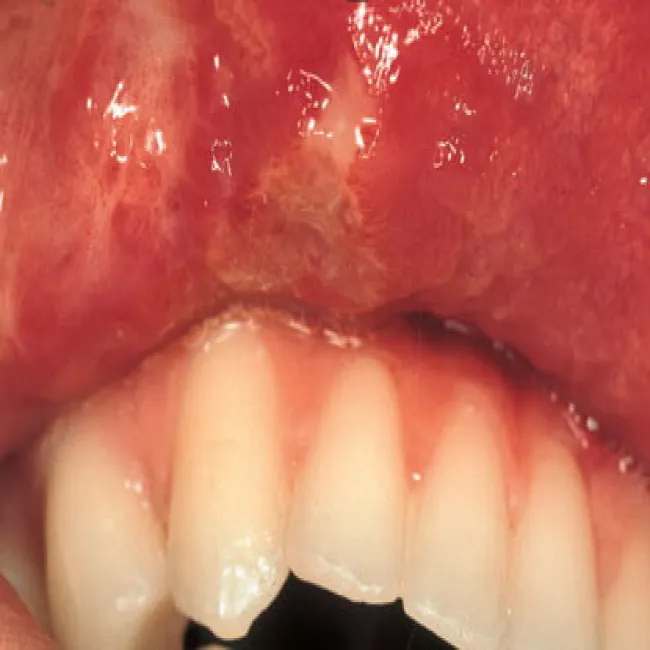

Choroba Behçeta na wardze górnej

Choroba Behçeta

Jama ustna